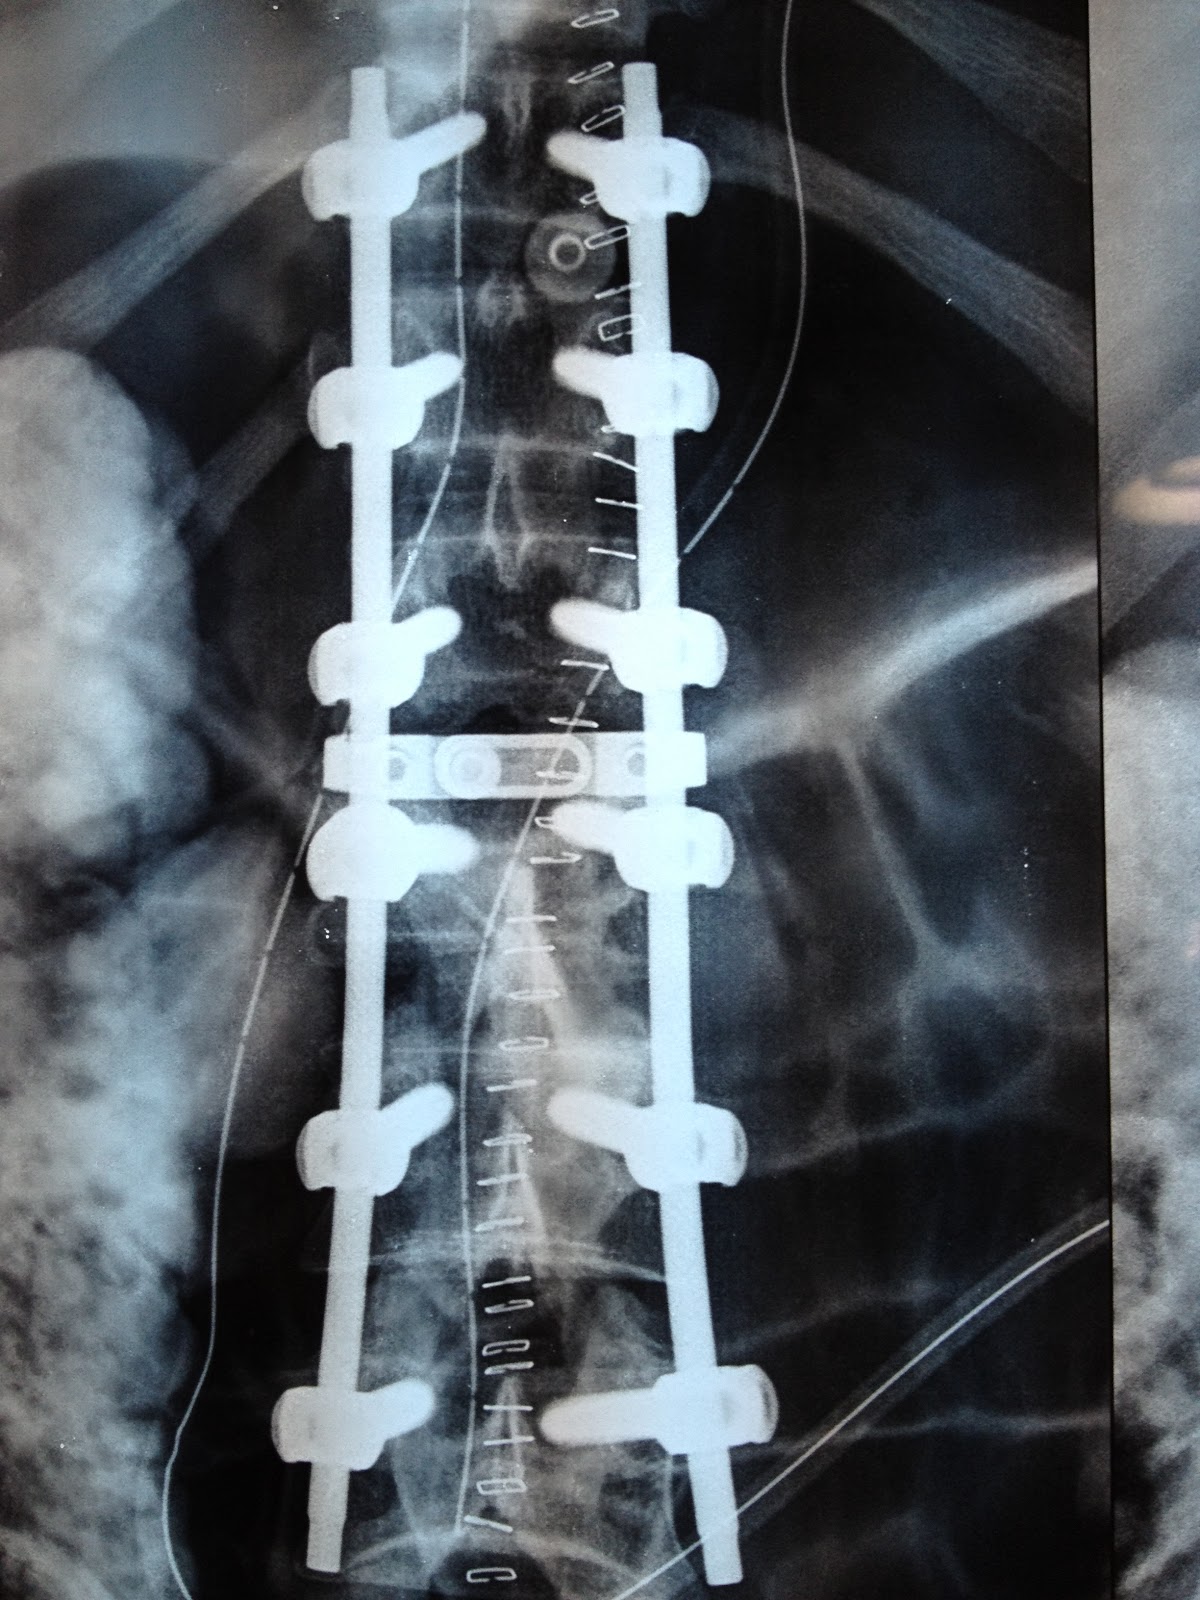

Figure2.Hole spine alignment. SVA Sagittal vertical axis, PI Pelvic

Figure2.Hole spine alignment. SVA Sagittal vertical axis, PI Pelvic What Causes Hole In Spine Many cases are associated with a. A csf leak may occur if there’s a tear or a hole in the dura mater. Syringomyelia has several possible causes. When it does, it can damage the spinal cord and cause pain, weakness and stiffness. Spinal stenosis is a narrowing of the spinal canal, the opening created by the small hole found in. What Causes Hole In Spine.